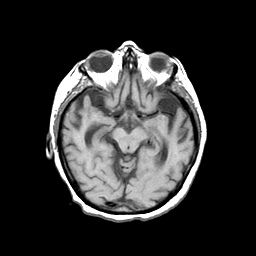

Basal Ganglia Calcification: T1-weighted MR -- Slice #7

[Home][Help][Clinical] Slice 7